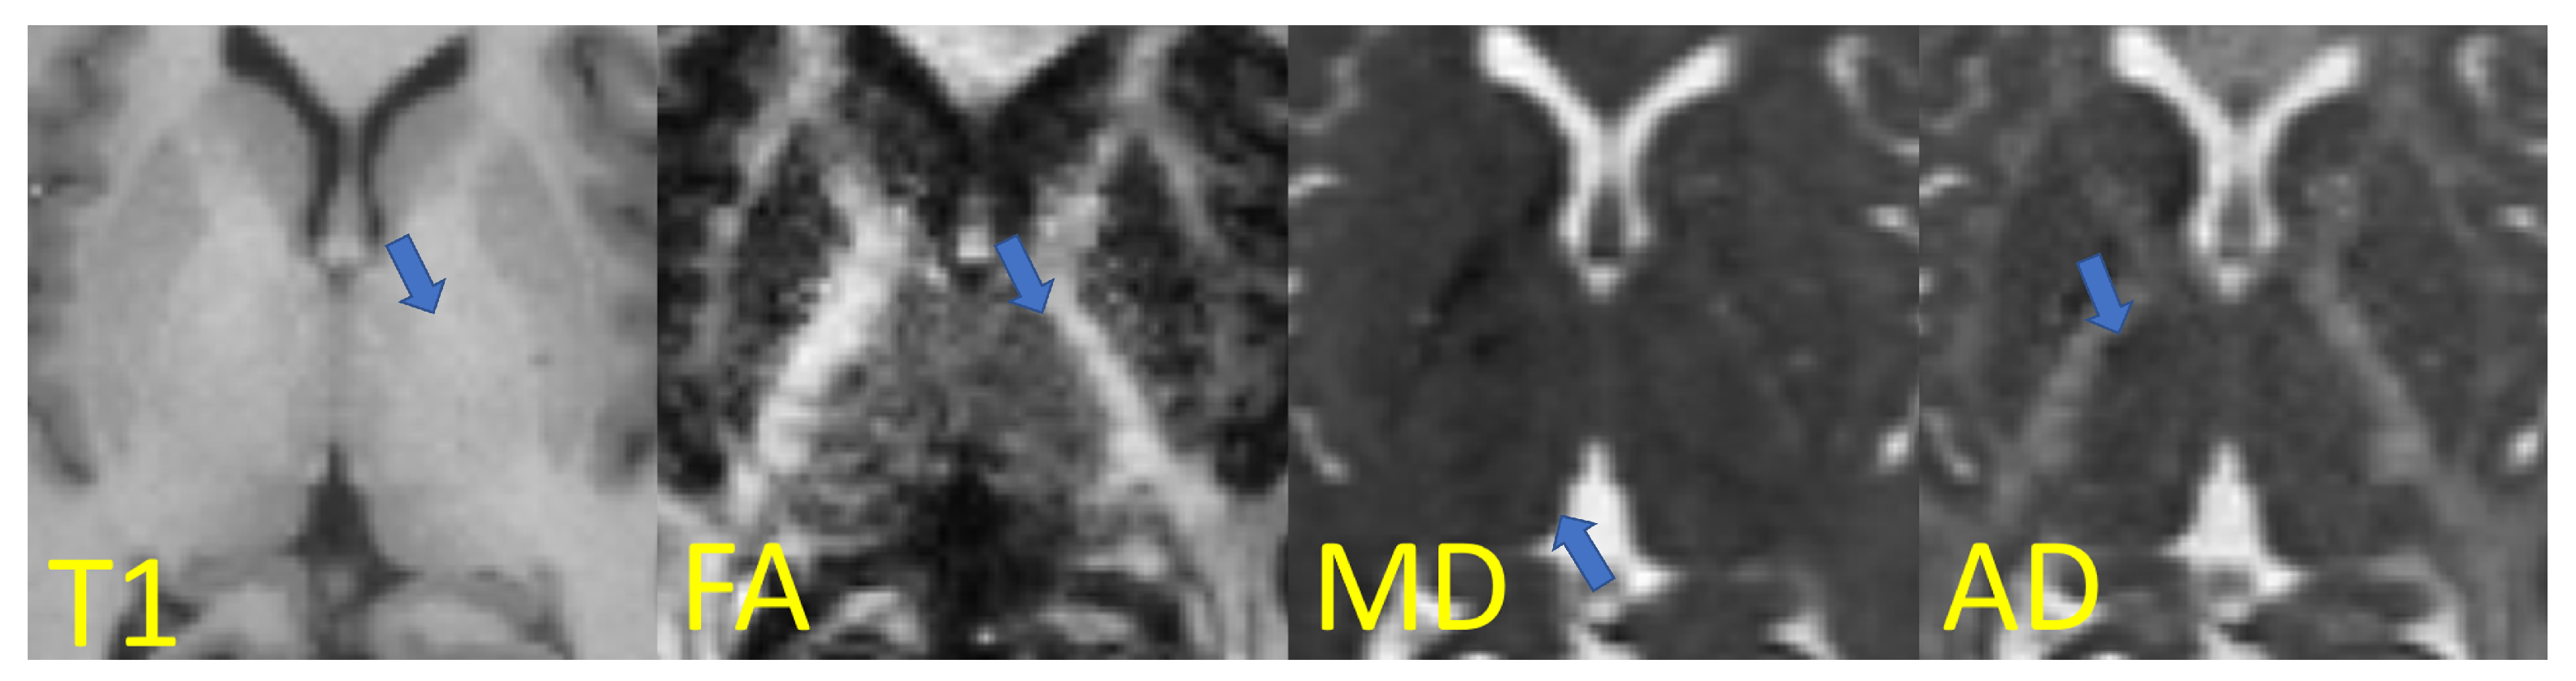

Figure 3.

Axial slices in the thalamus region with thalamic borders highlighted (areas pointed by the arrows): T1-weighted image and examples of diffusion indices (fractional anisotropy, mean diffusivity, and axial diffusivity) from diffusion tensor imaging. Adapted with permission from Ref. [26]. 2021 Society of Photo-Optical Instrumentation Engineers (SPIE).

For example, when visualizing scalar maps computed from diffusion tensor imaging (Figure 3), the frontiers of the thalamus with other structures are clearly visible: on FA maps, for instance, the boundary between the thalamus and internal capsule is shown with a higher contrast due to the differing anisotropic diffusivity of these structures.